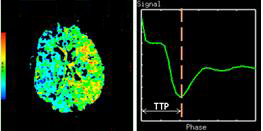

Time to Peak

Time To Peak is inversely related to CBF in which reduction of blood flow results in an increase in the time needed for the contrast to reach its peak in brain tissue.